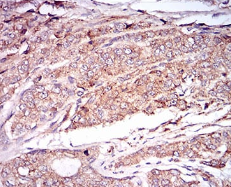

IHC    1/100 - 1/500